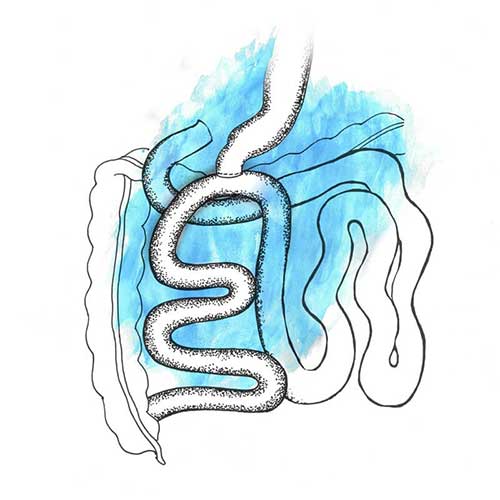

Laparoscopic banded gastric bypass is a reversible weight-loss procedure which involves stapling off a section of the stomach, thereby creating a pouch and reducing the stomach size. This allows food to bypass the beginning of the small intestine, which is the duodenum and part of the jejunum. In addition, a silicon ring is placed over the pouch to prevent dilatation of the pouch. Post surgery, your appetite reduces, as you feel satiated with smaller portions of food.

Laparoscopic banded gastric bypass is the procedure of choice for those who have severe acid reflux and/or high cholesterol. Patients who have suffered from diabetes for over 10 years also benefit from this surgery. This is also an excellent procedure to reduce BMI in order to achieve and maintain better weight loss. It may also be recommended to individuals who have persistent acid reflux and/or weight regain after a sleeve gastrectomy.

You will not be able to eat as much as you did prior to the surgery. You must also be careful about the ‘dumping syndrome’ that occurs in some patients post the surgery. This is when food passes too quickly into the intestine, causing nausea, cramping, bloating, dizziness, etc. Generally, it is triggered by eating high-calorie foods such as sweets and certain carbohydrate sources. This procedure also requires compliance with lifelong supplementation. In extremely rare cases, constant overeating can cause the silicon ring to enter the stomach, necessitating an endoscopy for its removal.

Laparoscopic mini gastric bypass is a variant of the gastric bypass surgery. It sees a loop of the small intestine being joined to the stomach pouch at a distance of 150 to 200 cm.

It is the procedure of choice for patients who do not suffer from gastroesophageal reflux disease and are aged above 50. It may also be recommended for patients on multiple anti-depressants or anti-psychotic medication.

Like other procedures, nearly 60 to 80 per cent of your excess body weight will reduce over a period of one-and-a-half years with rapid weight loss during the first three to four months after surgery. Though the chances of regaining the lost weight are negligible, it is possible if you do not follow a healthy lifestyle according to our recommendation.

Post-surgery, vitamin and mineral supplements need to be taken regularly and for life. Overconsumption of high-calorie liquids or foods may cause diarrhea. There is also a possibility of marginal ulcers and bile reflux, causing abdominal discomfort.

This procedure involves creating a sleeve by surgically removing two-thirds of the stomach portion and then also bypassing the first 100 - 150 cms of the small intestine. It is then joined as a loop to the first part of the small gut, which is the duodenum.

Laparoscopic duodenojejunal bypass is the procedure of choice for patients with lower BMIs but suffering from diabetes. It is also recommended for patients who have undergone a sleeve gastrectomy and have either regained weight or have been diagnosed with severe diabetes once again.

Nearly 60 to 80 per cent of your excess body weight will reduce over a period of one-and-a-half years. Rapid weight loss will occur within the first three to four months after surgery. Thereafter, the weight loss rate will slow down. However, if you do not follow a fitness regime combined with healthy diet and regular follow-up, you are most likely at the risk of regaining your lost weight soon.

Post-surgery, vitamin and mineral supplements need to taken regularly, for the rest of your life. Eating high-calorie foods could cause diarrhea in some patients.

SADI involves bypassing almost the entire length of the small intestine, leaving only 200–250 cms for nutrient absorption.

This is a second-stage procedure for heavily obese patients who require additional weight loss of about 30 to 40 kgs, and who have already undergone a primary procedure such as sleeve gastrectomy.

Weight loss occurs in the first six months post surgery, after which it stabilizes, approximately one-and-a-half years after the procedure.

Protein supplementation as well as vitamin and mineral supplementation are non–negotiable post this surgery. Fat-soluble vitamins such as A, D, E and K need to be replaced. Patients who undergo this procedure must be willing to commit to high levels of supplementation for their lifetime. Some patients may complain of diarrhea and flatulence post surgery.